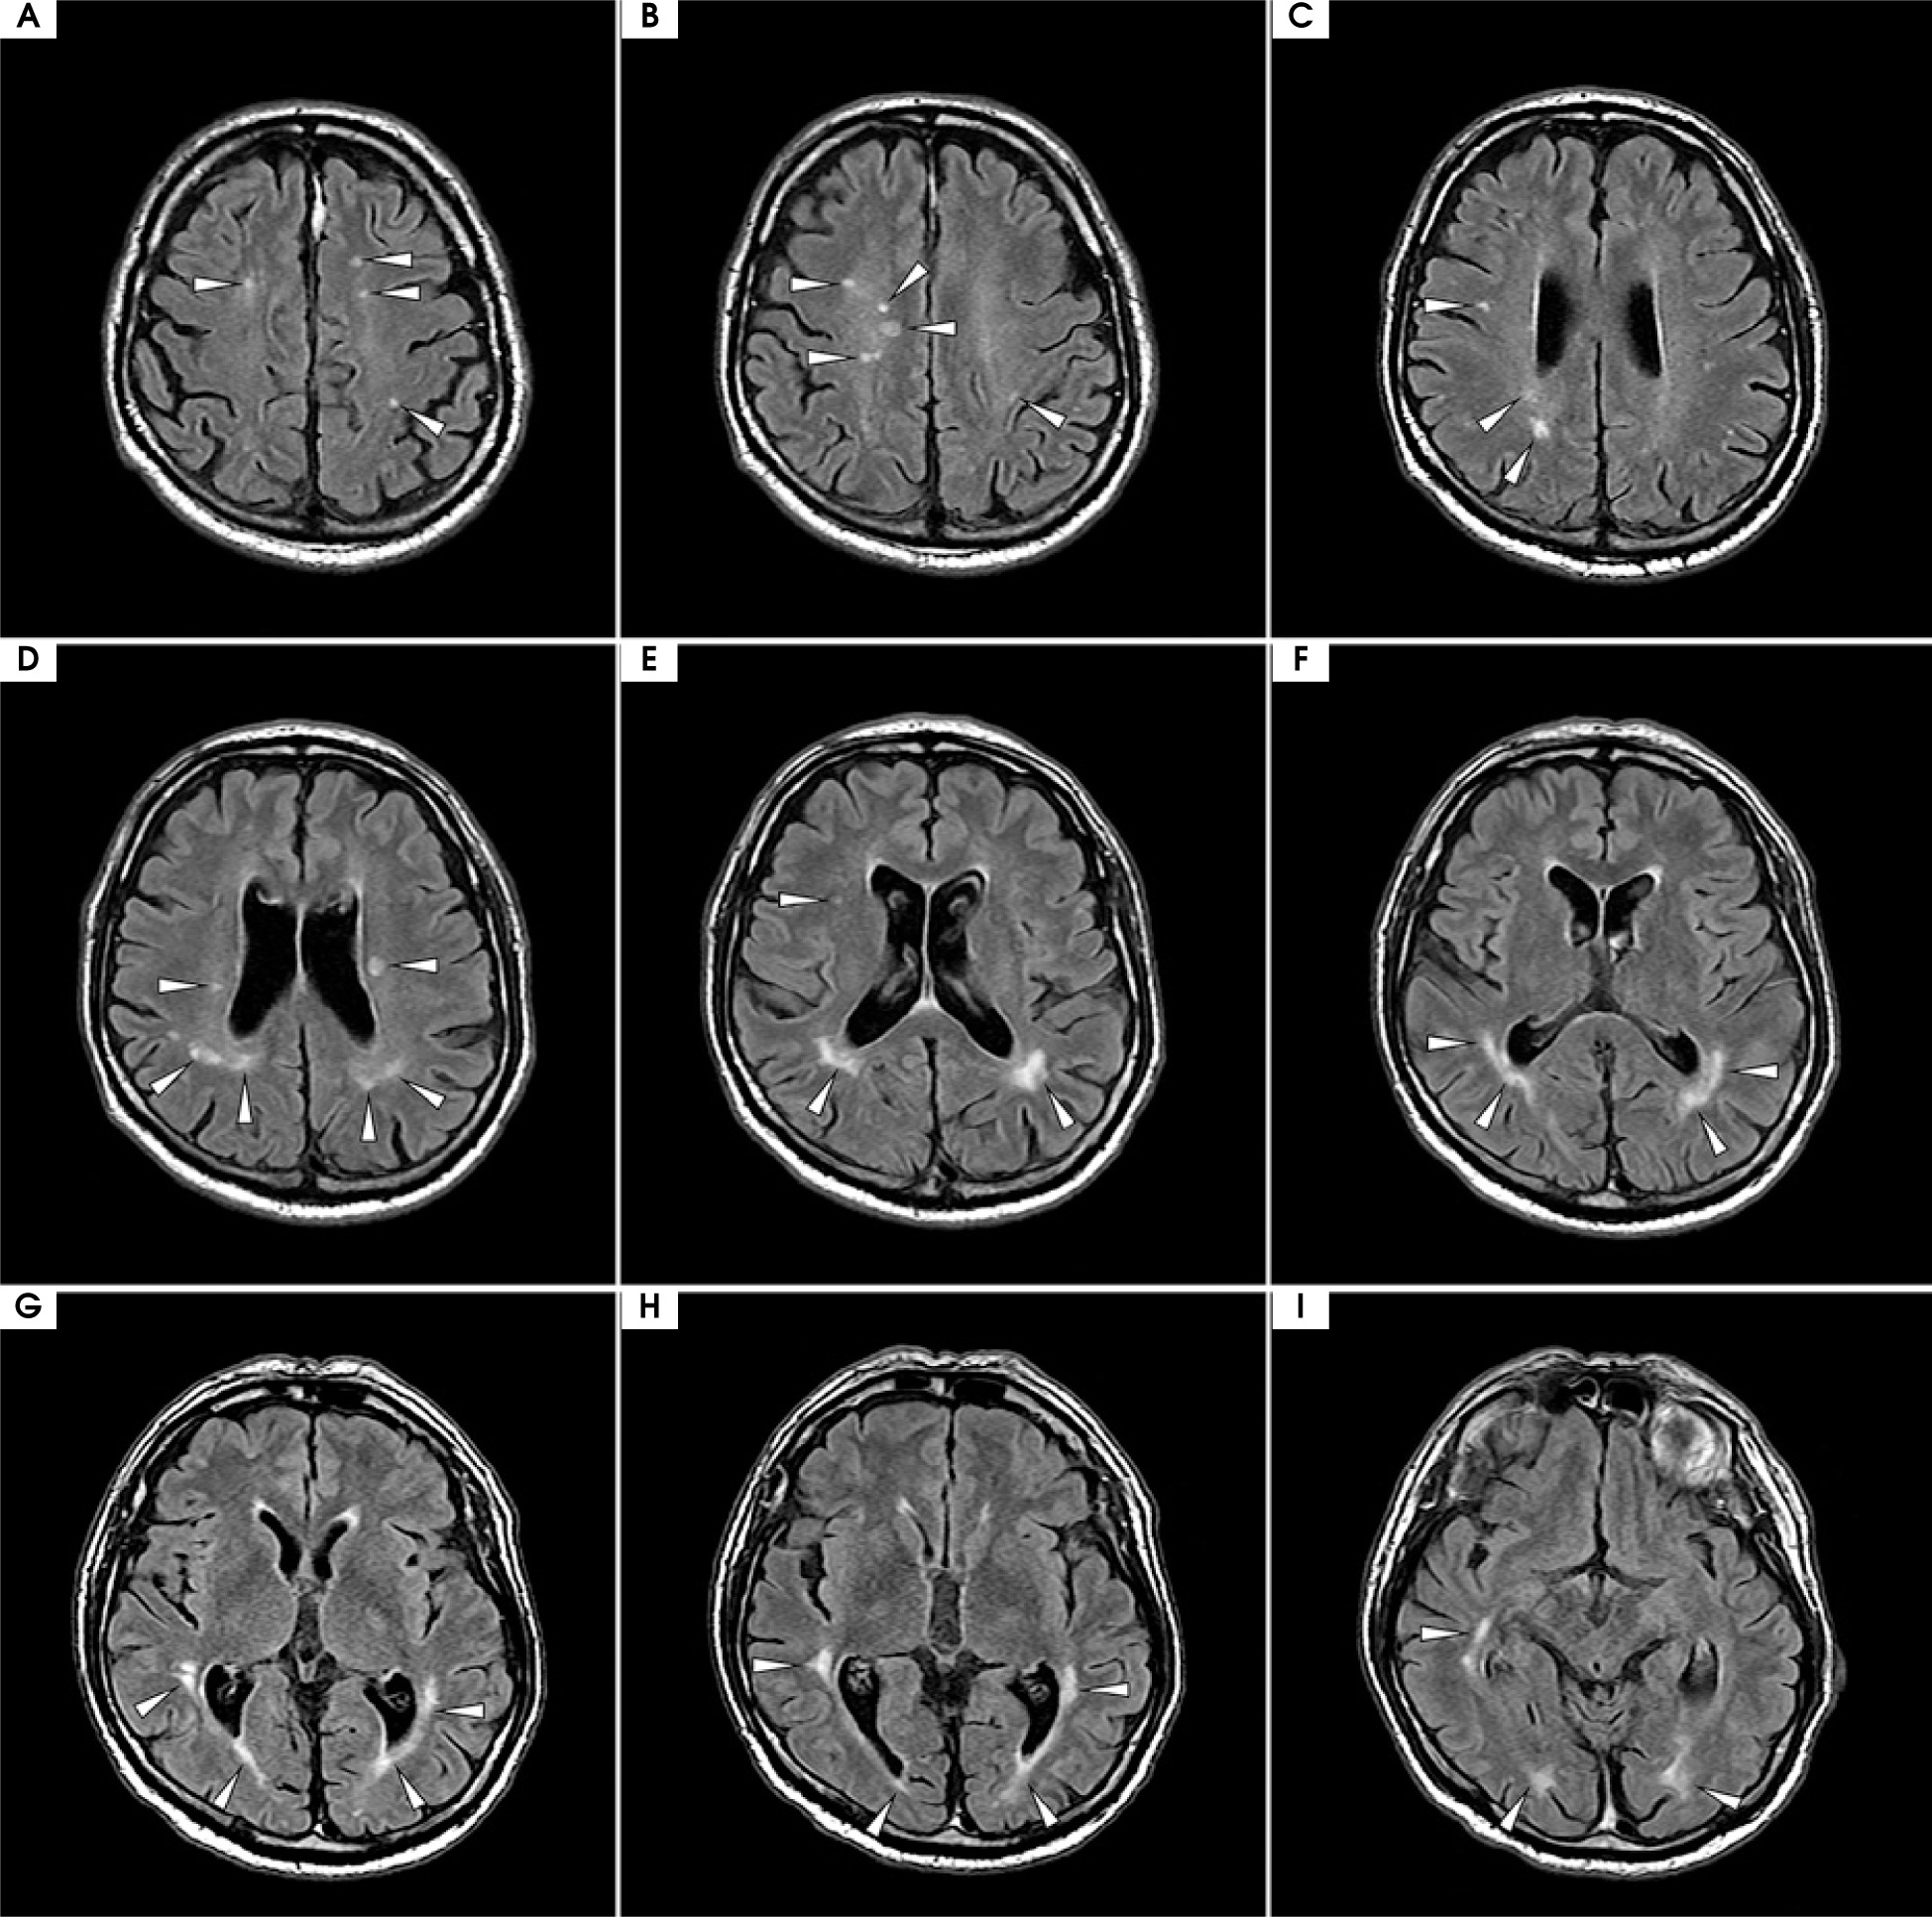

Figure VI

Magnetic resonance imaging (MRI) with contrast from the follow-up visit in December 2024; axial projection, fluid-attenuated inversion recovery (FLAIR) sequence. Slices in a cranio-caudal sequence. Compared to the previous follow-up scans shown in Figure II, the scan revealed minimal evolution of supratentorial hyperintensities, which persisted despite minimal clinical symptoms and a satisfactory response to maintenance treatment. No new hyperintensities were observed compared to the previous follow-up MRI from the year prior. Similarly to previous studies, no contrast enhancement or diffusion restriction of the hyperintensities was noted